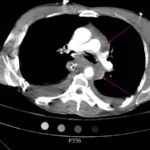

The initial chest x-ray showed an abnormal superior mediastinal contour (blue line), suggestive of a possible aortic injury. The CT angiogram showed extensive circumferential irregularity and outpouching of the distal aortic arch (red arrows) compatible with aortic transection. In addition, there was a circumferential intramural hematoma, which extended through the descending aorta to the proximal infrarenal abdominal aorta (green arrow). There was also an extensive surrounding mediastinal hematoma extending around the descending aorta and supraaortic branches (purple arrows).